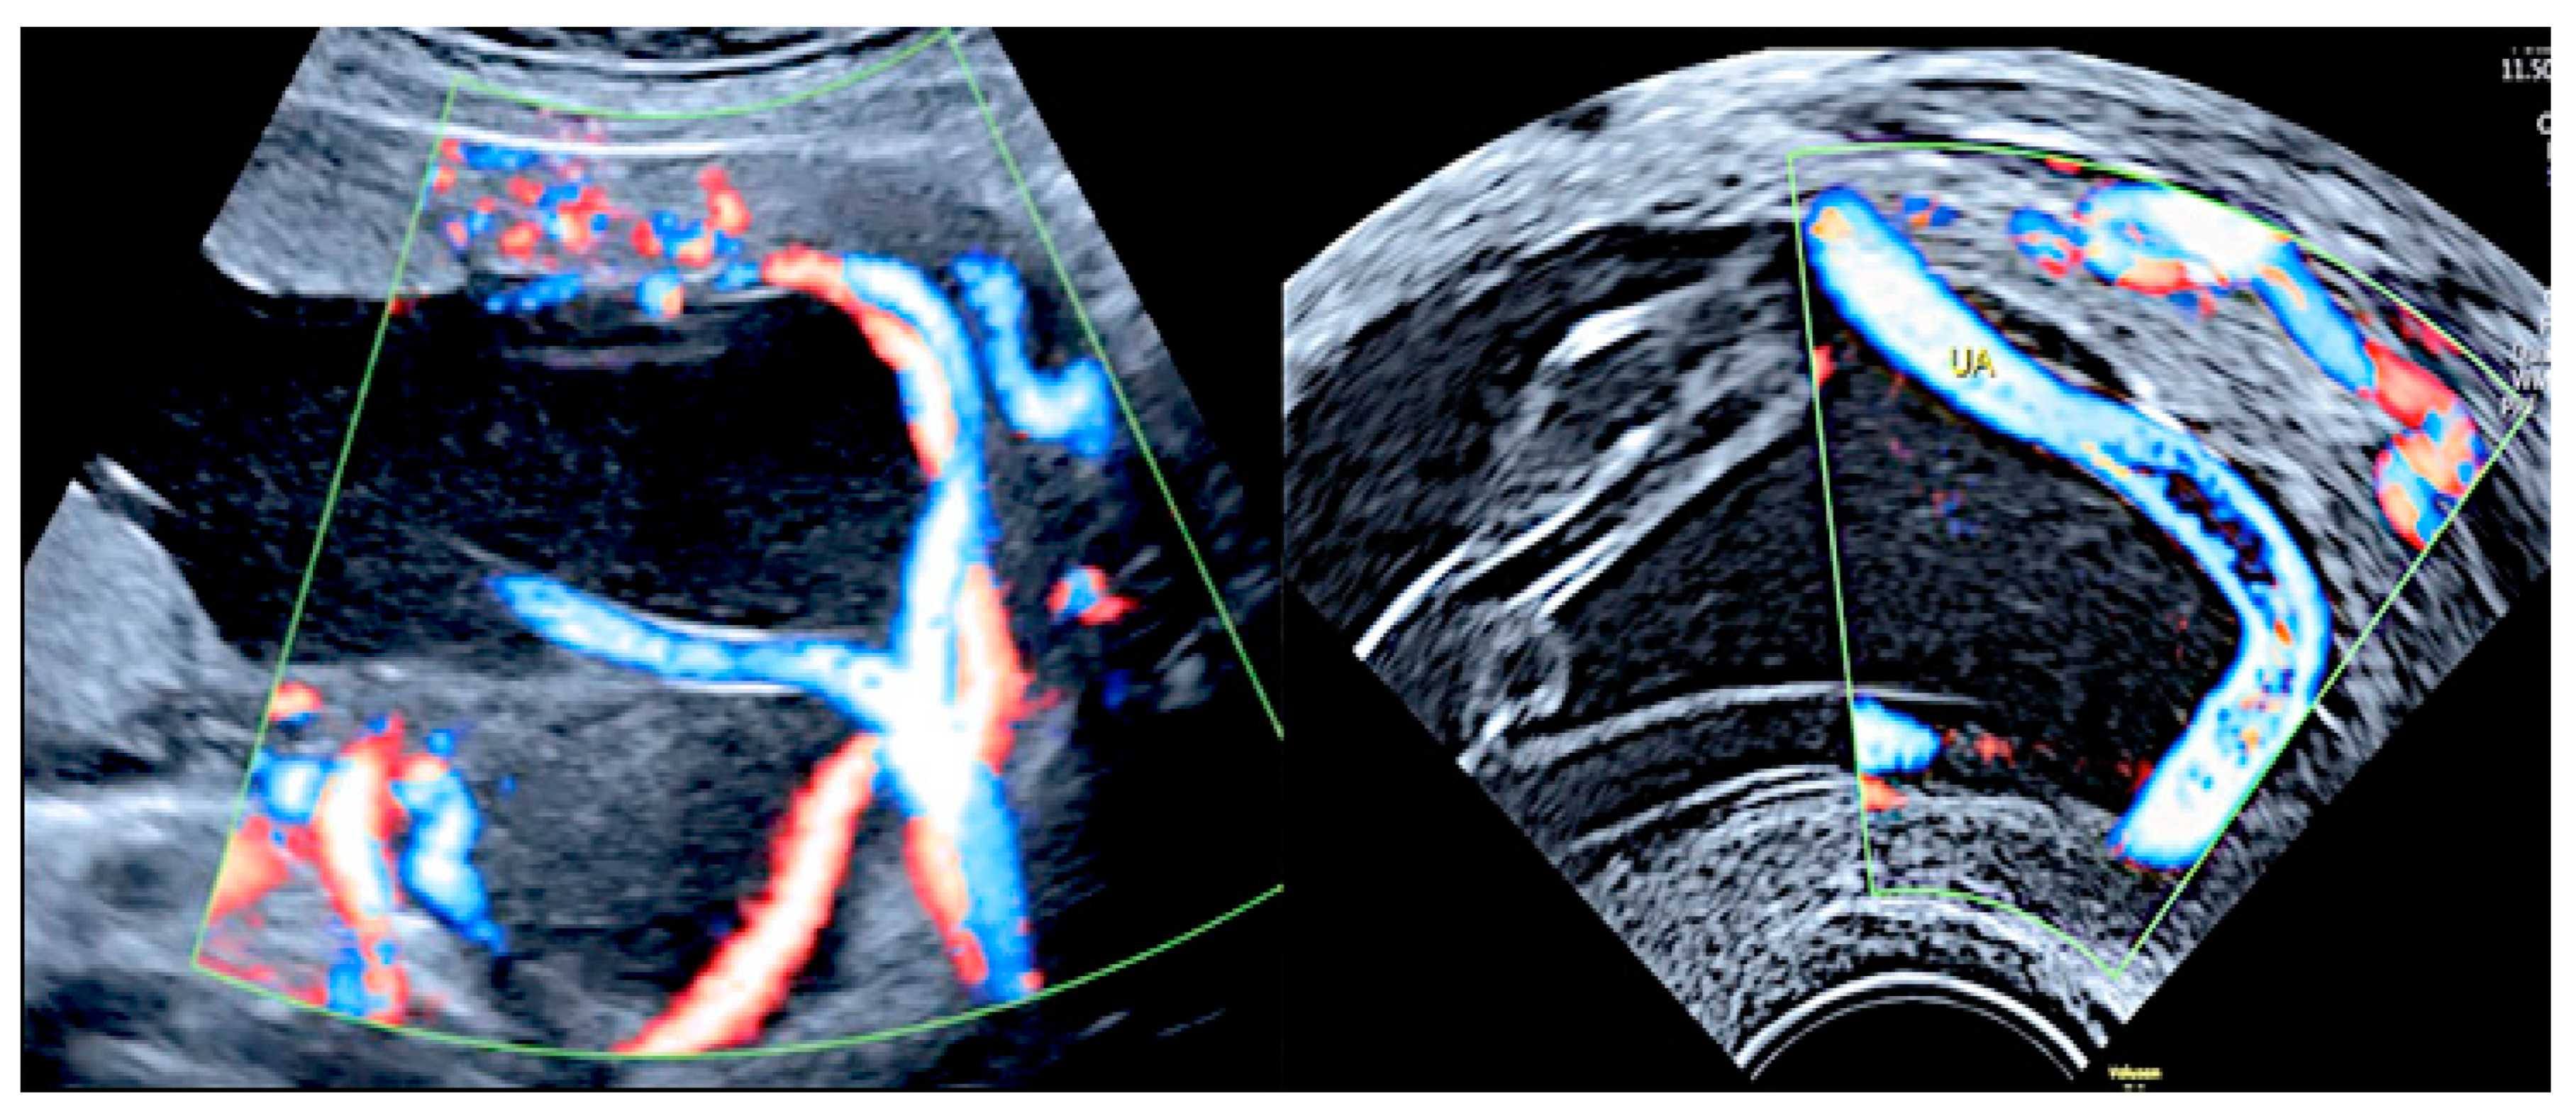

3.1.3. Bilobed Placenta and Succenturiate Lobe

Two-dimensional color Doppler ultrasound and three-dimensional ultrasound using HD-Live™ flow showing a bilobed placenta. When an accessory lobe is detected (succenturiate) in the lower part of the uterus, careful evaluation with ultrasound for vasa praevia and velamentous cord insertion should be performed.

Pregnancy at 20 week’s gestation. Two-dimensional color Doppler ultrasound showing velamentous insertion in a bilobed placenta. (Legend: UA, umbilical artery).